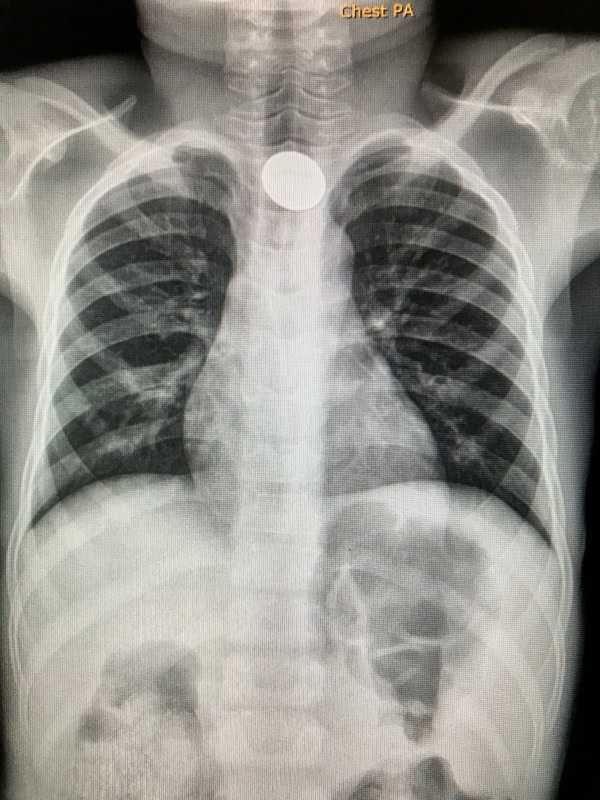

In the print version of the book there are many black and white images. The full colour versions are found in the gallery below. Depending on your connection performance the enlarged images may take a little time to load.